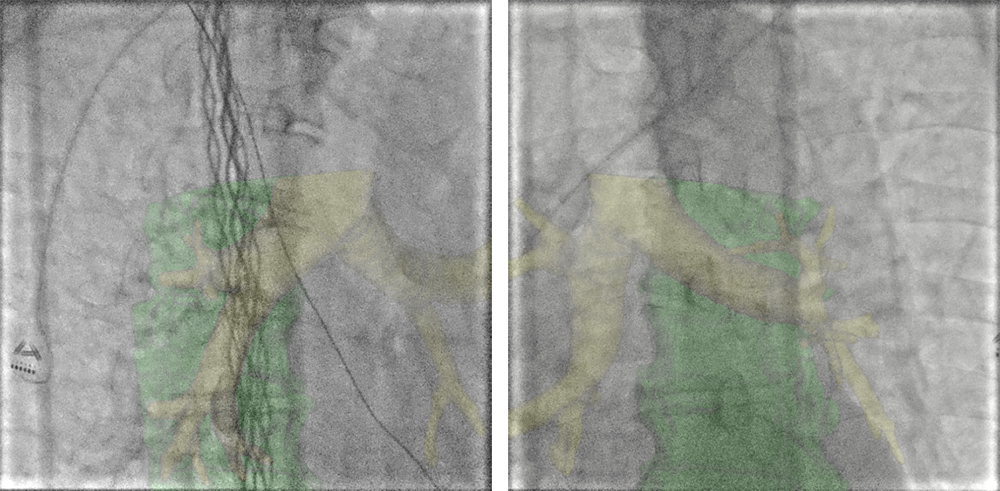

③ 不整脈治療

透視条件設定

不整脈治療時の透視条件は、フレームレート7.5fpsの設定にしています。早い動きに対応する必要性の少ない手技ではありますが、3.75fpsでは細かなカテーテル操作に対応が困難であったため、7.5fpsを選択しました。下に当院での透視条件設定を示します。この設定条件において、指頭型電離箱を用いて臨床と同じ配置での線量率を計測しました。FOV20cm、SID100cm、PMMA20cmでの患者照射基準点における透視線量率は1.61mGy/minでした。ただし、体格や角度によって視認性が低下する事が予想される場合や、詳細な透視画像を求められる場合に備え、線量や画像処理の異なる複数の設定をプリセットしています。なお、手技中に設定変更を行ってもFPDキャリブレーションが実施されないため、手技の妨げとなることはありません。

IGS620_kurume_08.jpg